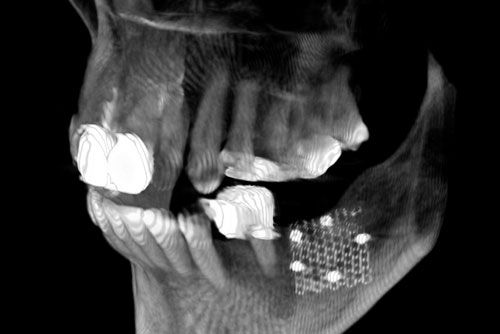

Augmentation bezeichnet die Vergrößerung bzw. Verbreiterung des Knochenlagers zur Aufnahme von Implantaten oder einfacher – die Regeneration von Kieferknochen. Dazu verwendet man entweder körpereigenen Knochen oder ein synthetisches Material. Eigenknochen-Transplantationen haben den Vorteil der unkomplizierten Einheilung, da Ihr Körper in diesen Fällen keine Abstoßungsreaktion zeigt. In unserer Praxis ist es möglich, Ihren eigenen Knochen mittels Ultraschalltechnik schonend zu verpflanzen.

Ist das gesamte Knochenangebot für eine Eigenknochenverpflanzung zu gering oder die Entnahme in individuellen Fällen zu riskant, so gibt es die Möglichkeit, synthetische Materialien einzusetzen. Dabei greifen wir ausschließlich auf zugelassene, in Deutschland oder der Schweiz produzierte und bewährte Produkte zurück. Die Behandlungsmethoden unserer Praxis sind streng nach dem Prinzip der Evidence Based Medicine (EBM) und den Leitlinien der Deutschen Gesellschaft für Implantologie (DGI) ausgerichtet.